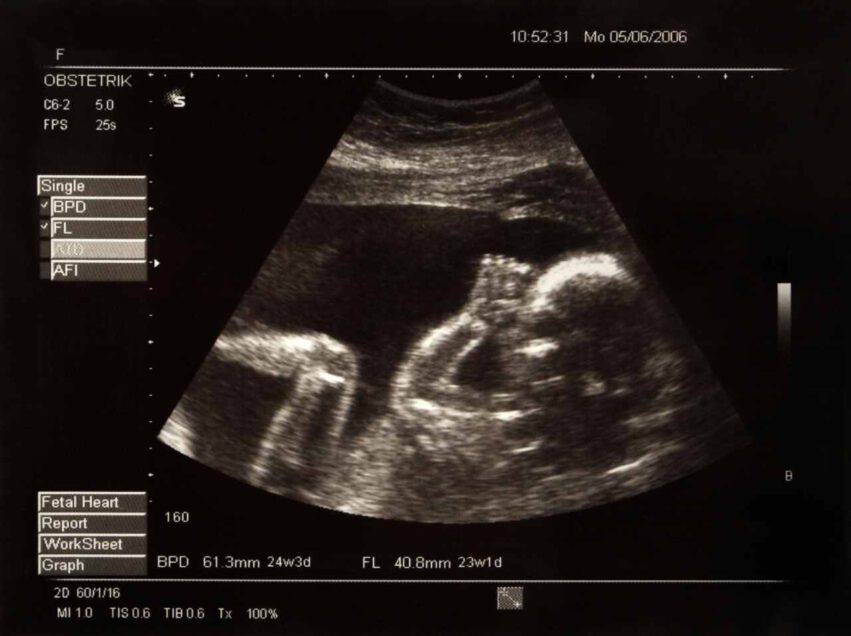

La donna è andata a fare un’ecografia prenatale alla dodicesima settimana di gravidanza temendo che, dal momento che Nathan non avrebbe potuto vedere la foto del piccolo, ci sarebbe rimasto male.

Nathan Edge ha dichiarato a People: “quando siamo tornati a casa abbiamo mostrato le scan a tutti ed erano tutti molto eccitati all’idea di vedere il bimbo per la prima volta. Essere non vedente di rado mi deprime, ne sono venuto a patti molto bene, ma ad un certo punto mi ha colpito: non potrò mai vedere questa ecografia“.

Deb Fisher non credeva che sarebbe stato tanto difficile “c’erano tante cuciture e scuciture”. Lei si è anche consultata con un’ostetrica per chiederle quali sarebbero state le parti del bimbo che i genitori avrebbero guardato in particolare e che lei avrebbe potuto mettere in risalto.

Prima di questo fantastico regalo Nathan usava le descrizioni degli ultrasuoni degli altri per immaginare come sembrasse il bambino. “Ora però sono capace di costruire un’immagine del mio bambino, è fantastico, avrei potuto trascorrere tutta la vita senza sapere come fosse la sua ecografia”.